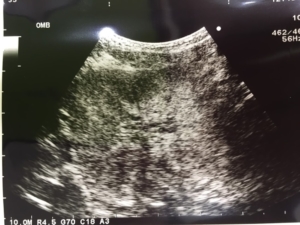

何かしらの変化があった場合は、腹部を触診するか、直腸検査を行って指で触知するかで仮診断を容易にすることが出来ますが、レントゲン検査とエコー検査を行ってさらに詳しい診断します。

エコー上では左右均等に前立腺が大きくなるため、診断は割とつけやすいと思います。